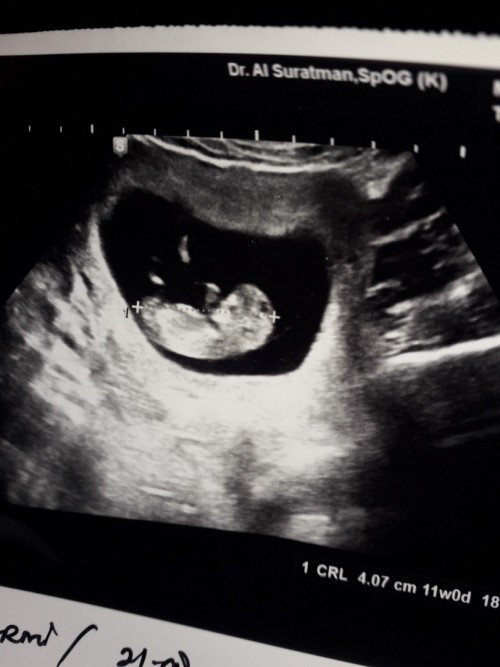

ini aku 11 minggu dah komplit kk bun

ini usg aku 10w pas.. bahkan udah ada denyut jantungnya bun.. dari usia 7w harusnya udah ada

saya 11 minggu udah kelihatan banget bun,kalo 10 seharusnya hampir sama cuma lebih kecil